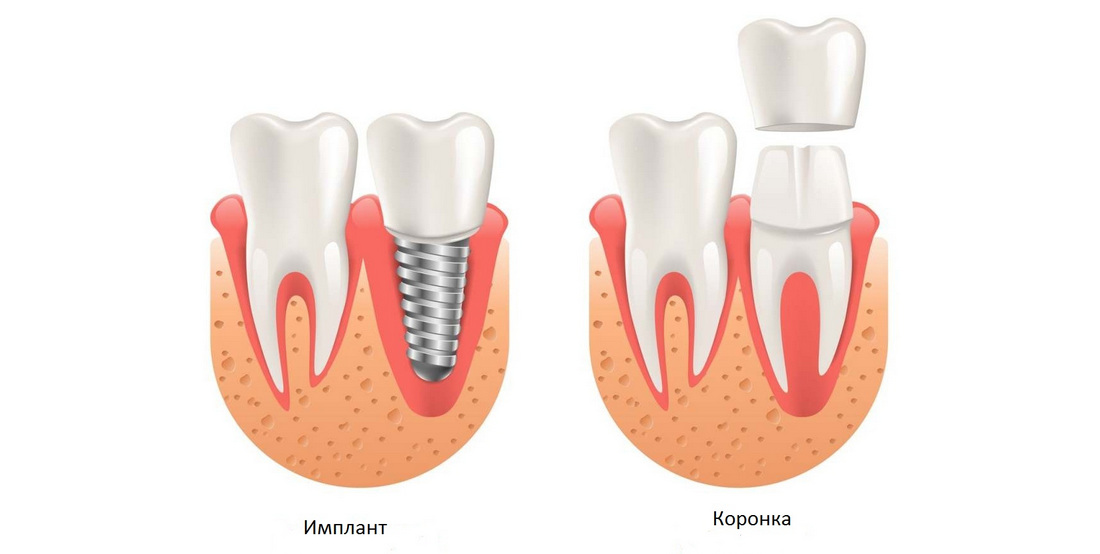

Современные коронки на зубные импланты: виды и фото-примеры